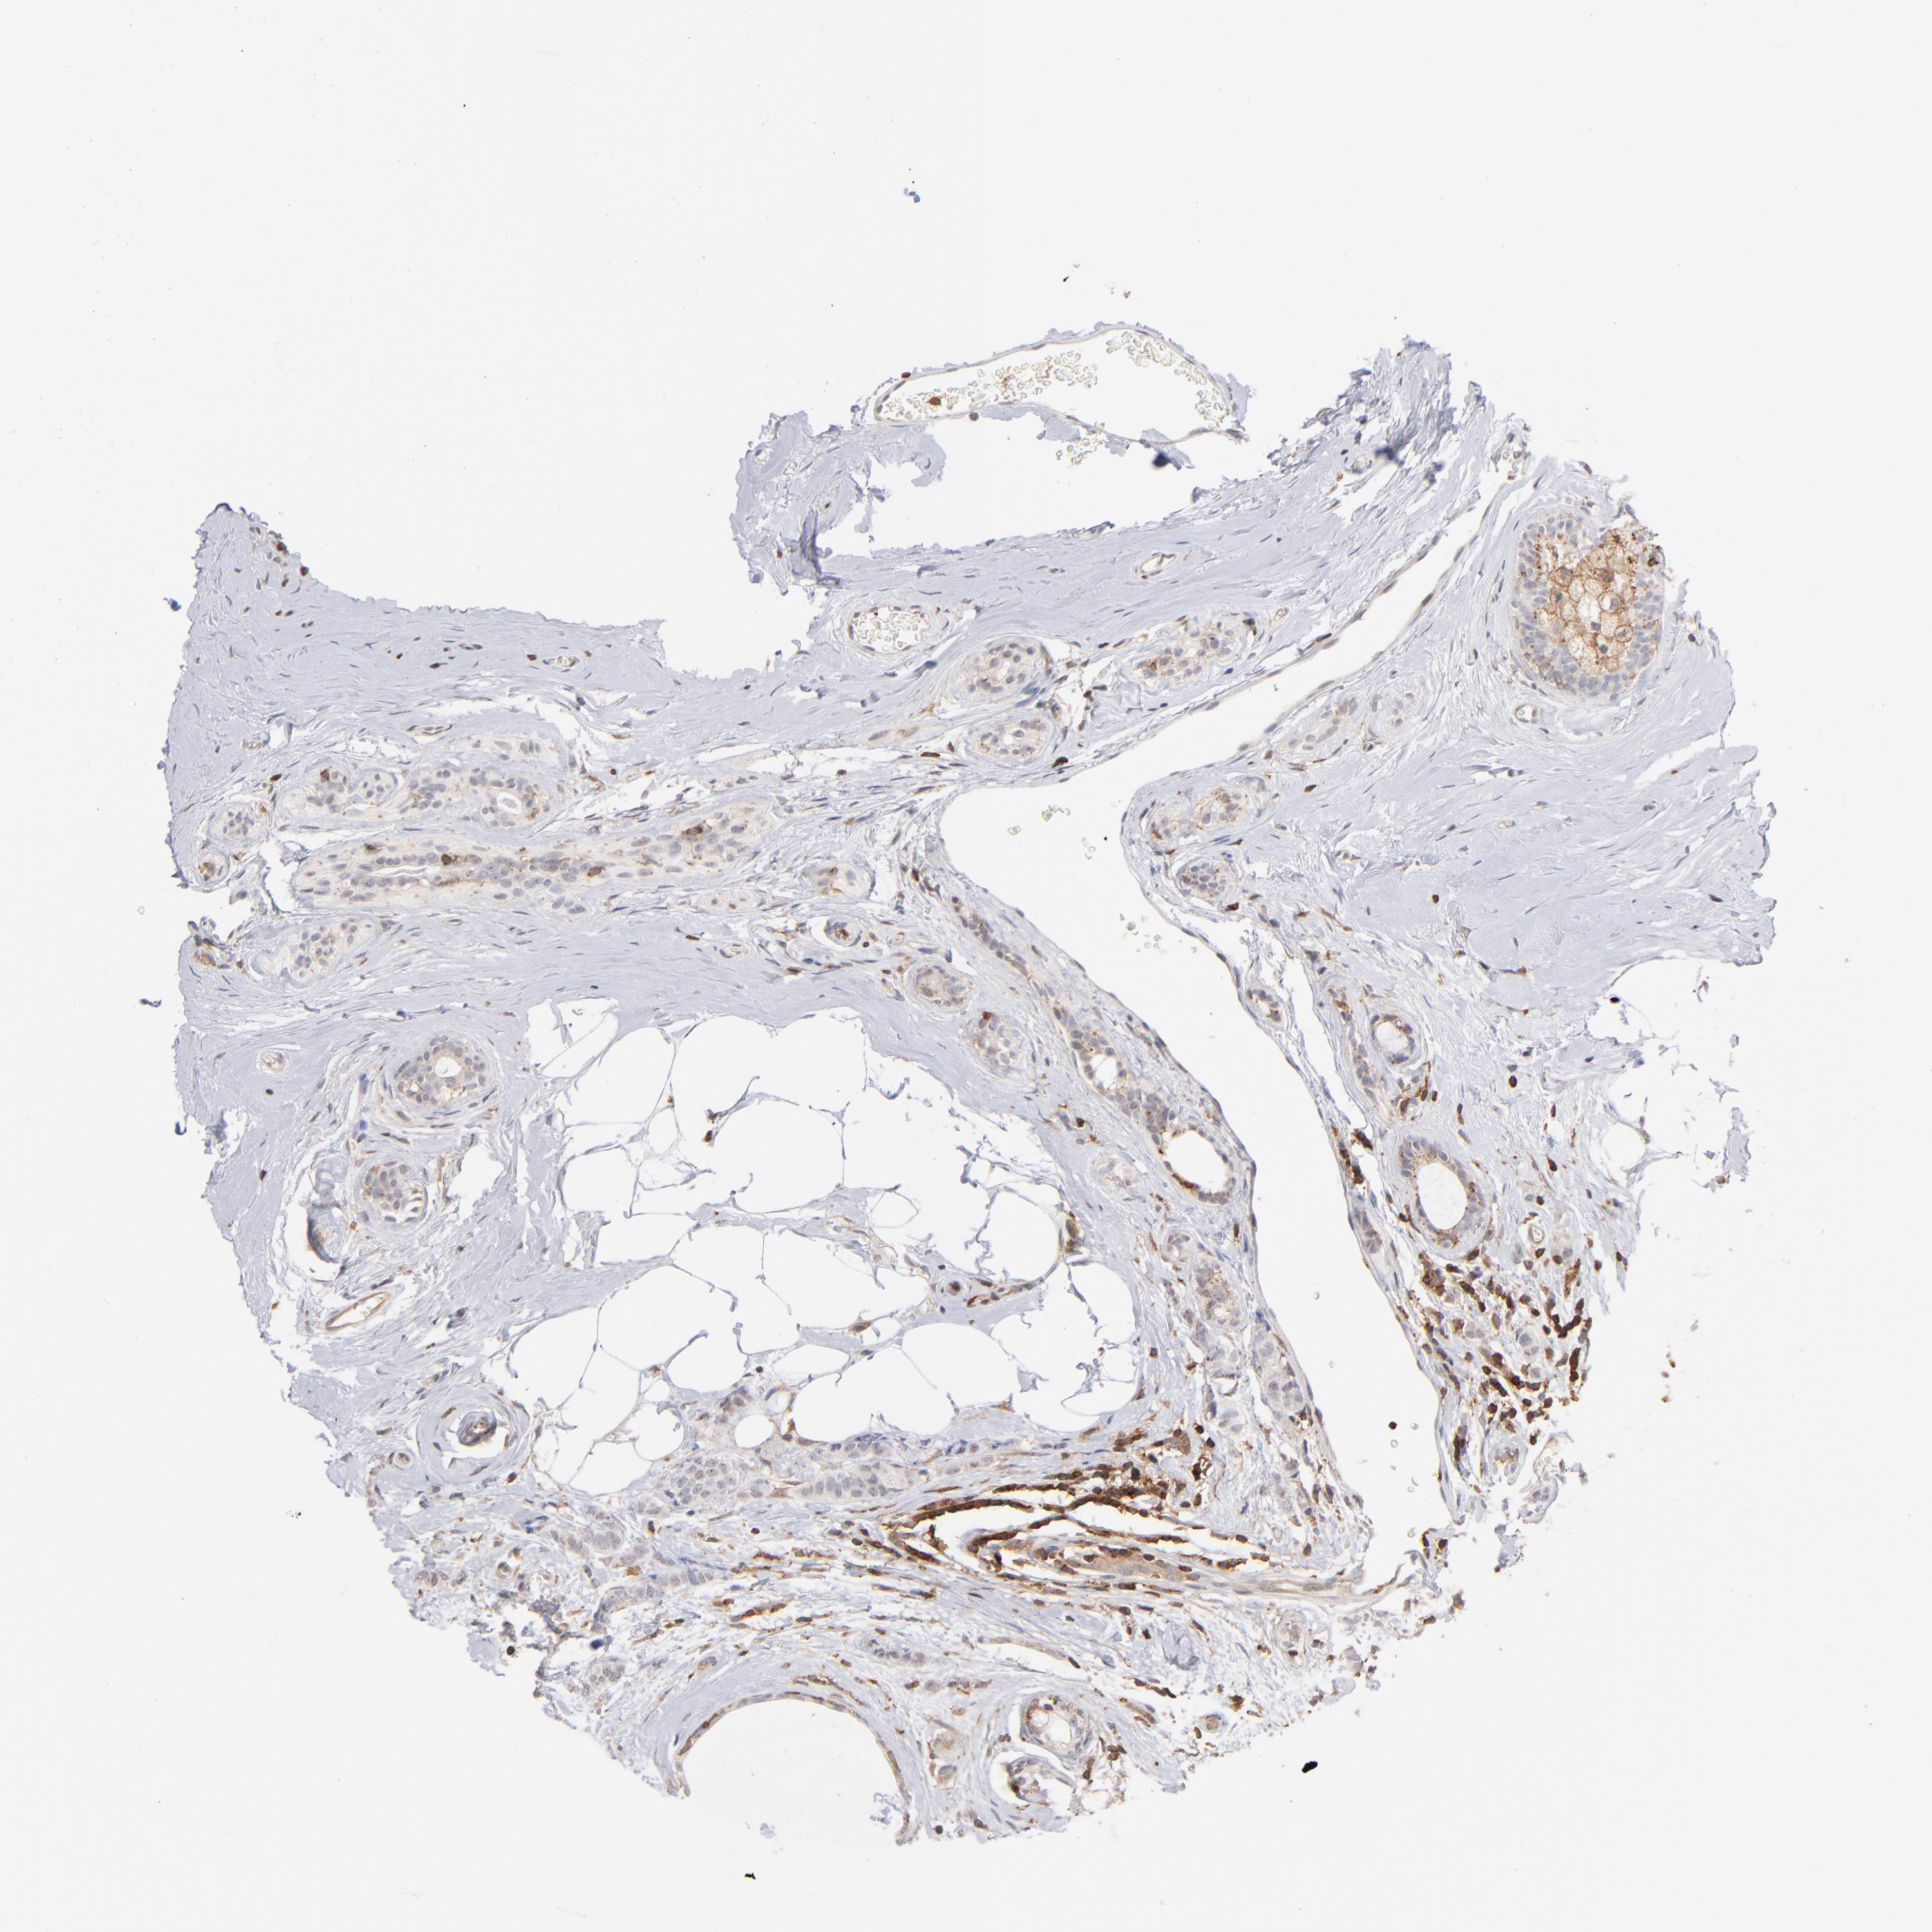

BRCA TCGA BRCA VALIDATION PROTEIN EXPRESSION

ANTIBODIES

AND

VALIDATION